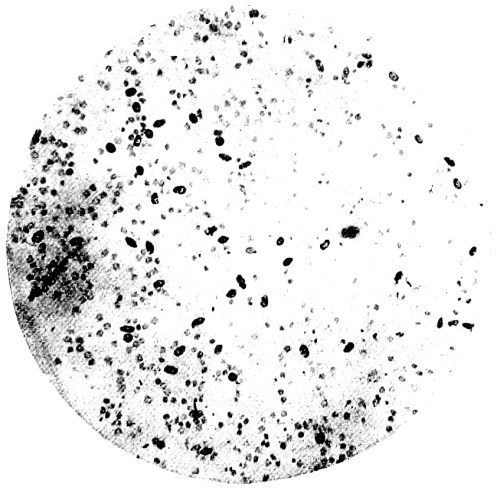

8. Measurement of Blood Corpuscles (human) 97

9. Measurement of Blood Corpuscles (sheep) 97